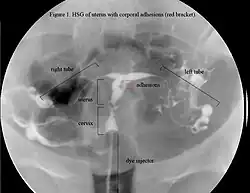

The history of a pregnancy event followed by a D&C leading to secondary amenorrhea or hypomenorrhea is typical. Hysteroscopy is the gold standard for diagnosis.[18] Imaging by sonohysterography or hysterosalpingography will reveal the extent of the scar formation. Ultrasound is not a reliable method of diagnosing Asherman's Syndrome. Hormone studies show normal levels consistent with reproductive function.

In an attempts to estimate the prevalence of AS in the general population, it was found in 1.5% of women undergoing hysterosalpingography HSG,[51] and between 5 and 39% of women with recurrent miscarriage.[52][53][54]